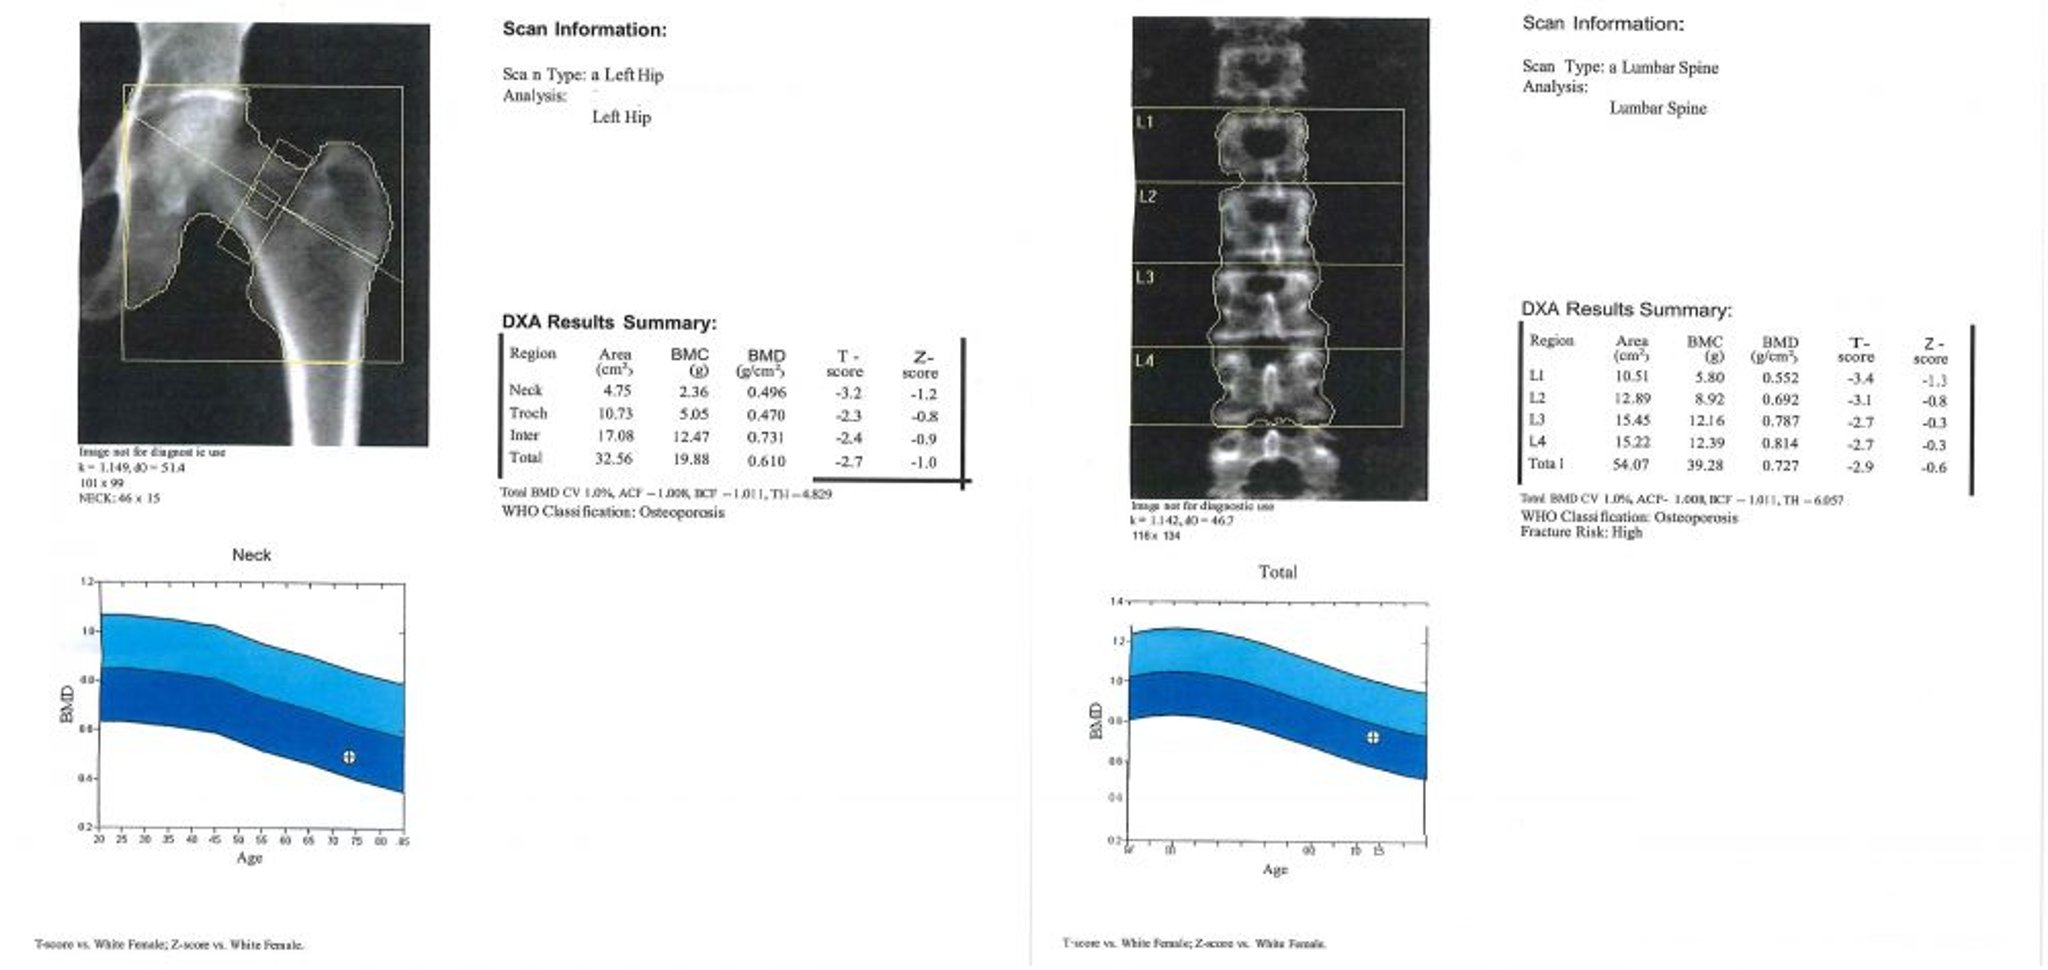

Двухэнергетическая рентгеновская абсорбциометрия (ДЭРА)

С целью скрининга людей с высоким риском, обеспечения количественной оценки потери костной массы, прогнозирования риска переломов и мониторинга состояния тех, кто проходит лечение, минеральная плотность костной ткани должна измеряться с помощью DXA-сканирования (1). При ДЭРА-сканировании целевые участки, как правило, позвоночник и одно или оба бедра, визуализируются с помощью рентгеновского излучения высокой и низкой энергии (отсюда и термин «двойная энергия»). Разница в ослаблении лучей высокой и низкой энергии является отражением содержания минералов в костях. Содержание минеральных веществ в костях, деленное на площадь костной ткани (также измеряется по данным ДЭРА-сканирования), представляет собой минеральную плотность костной ткани в г/см2. Наличие выраженного остеоартрита в целевых областях может увеличить зарегистрированный показатель плотности кости.

Результаты ДРА регистрируются в виде показателей T и Z.

Показатель Т соответствует числу стандартных отклонений, на которые минерализация кости отличается от ее пикового значения массы у молодых здоровых людей того же пола и расовой/этнической принадлежности. Всемирная организация здравоохранения устанавливает предельные значения для показателей Т, которые определяют остеопению и остеопороз (2). Показатель Т < -1,0 и > -2,5 определяет остеопению. При показателе Т ≤ -2,5 определяют наличие остеопороза.

Показатель Z соответствует числу стандартных отклонений, на какие минеральная плотность костей пациента отличается от человека того же возраста и пола, и должен быть использован для детей, женщин в пременопаузе, или мужчин, моложе 50 лет. Если Z-показатель ≤ -2,0 - минерализация костной ткани, для возраста пациента - низкая, и следует рассматривать вторичные причины потери костной ткани.